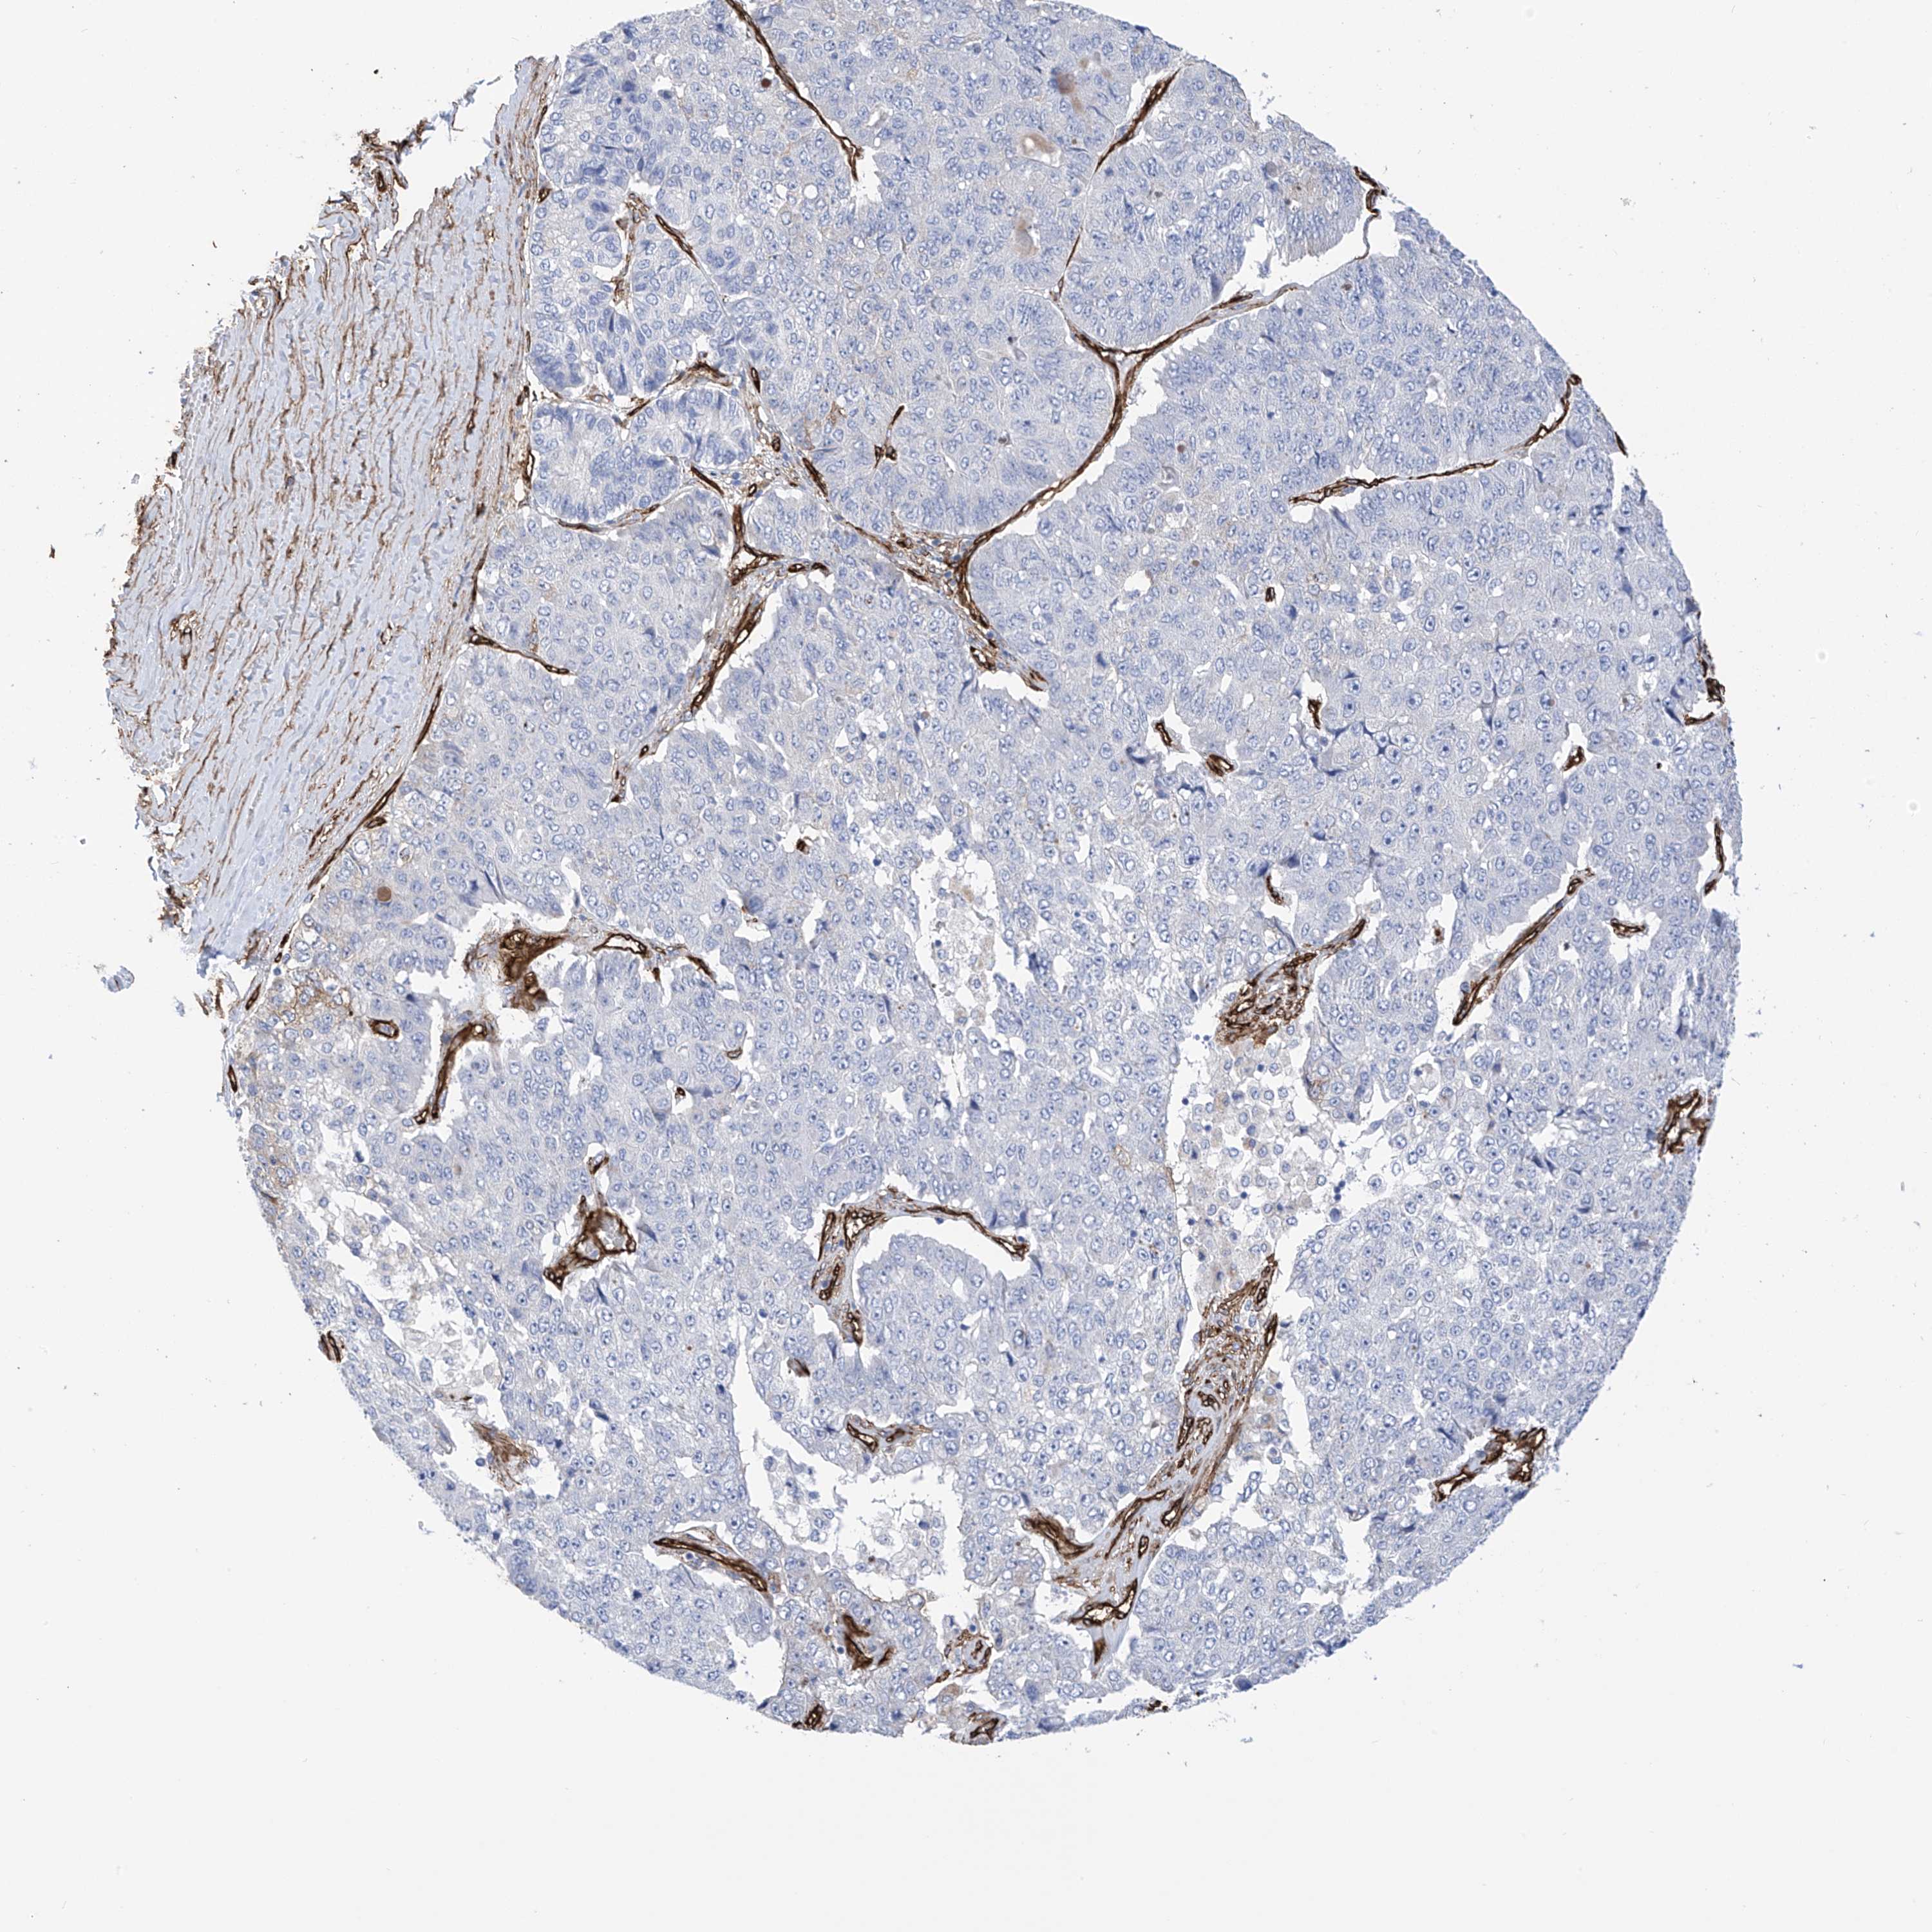

PANCREATIC CANCER - Protein expressioni

A mouse-over function shows sample information and annotation data. Click on an image to view it in a full screen mode. Samples can be filtered based on level of antibody staining by selecting one or several of the following categories: high, medium, low and not detected. The assay and annotation is described here.

Note that samples used for immunohistochemistry by the Human Protein Atlas do not correspond to samples in the TCGA dataset.

Antibody stainingi

Antibody staining in the annotated cell types in the current human tissue is reported as not detected, low, medium, or high, based on conventional immunohistochemistry profiling in selected tissues. This score is based on the combination of the staining intensity and fraction of stained cells.

Each image is clickable and will lead to virtual microscopy that enables deeper exploration of all samples and also displays staining intensity scores, fraction scores and subcellular localization as well as patient and tissue information for each sample.

Antibody HPA034825

Staining

High

Medium

Low

Not detected

Intensity

Strong

Moderate

Weak

Negative

Quantity

>75%

75%-25%

<25%

None

Location

Nuclear

Cytoplasmic/membranous

Cytoplasmic/membranous,nuclear

Adenocarcinoma, NOS